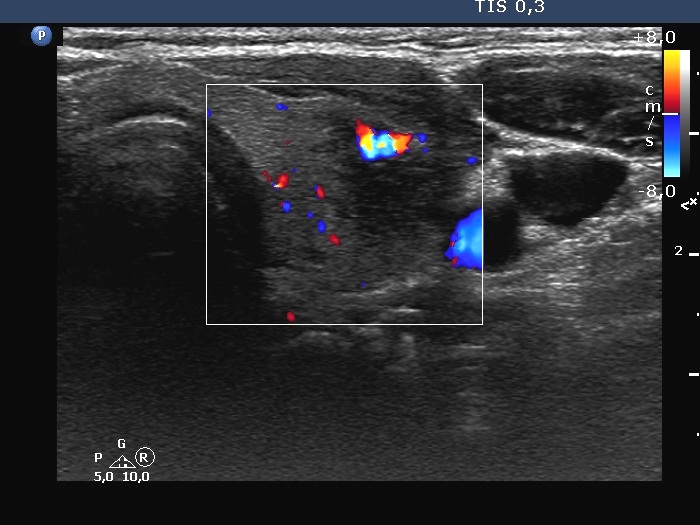

Second examination a year later (second row of images):

Ultrasonography. The thyroid has significantly decreased in size. The echogenicity became normal. The left lobe has already had discrete hypoechoic lesions but the size of them was much smaller compared with the previous visit.

3. if we had any doubts about the diagnosis after the first examination, it disappeared after the second visit: the size of the lobes decreased, the echogenicity became normal and although the discrete lesion has been already present, it also decreased in size.